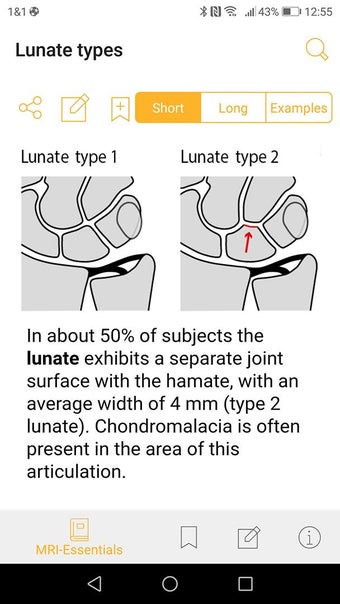

Jedes Thema wird in wenigen Seiten behandelt. Es gibt kurze Absätze mit einfachen Zeichnungen.

Die Basisversion liefert die wesentlichen Fakten, die immer noch kurz und prägnant sind. Die Fakten konzentrieren sich auf die klinisch relevanten Aspekte des Zustands des Patienten.

Die Pro-Version enthält mehr als 4.000 hochwertige Bilder von herausragender Bildqualität, die den Text veranschaulichen. Sie sind so konzipiert, dass sie dem Leser einen schnellen Überblick über die wichtigsten Informationen zum Zustand geben.